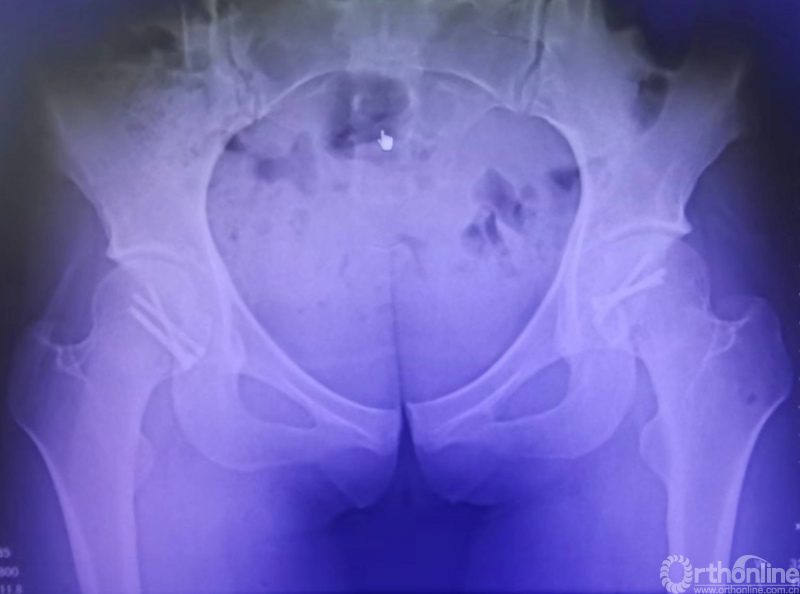

患者女,21岁,未婚。主诉车祸外伤致双髋部疼痛伴活动受限14小时入院。患者既往体健,无烟酒史及药物滥用史。

入院查体:生命体征平稳;双髋关节呈“弹性固定”位,即呈屈髋屈膝、内旋内收位,局部触痛明显,双髋关节活动障碍,双足动脉搏动可触及,双下肢末梢血运,各趾活动及触痛均正常。

骨盆CT示:双髋关节后脱位伴双股骨头骨折。

影像学检查